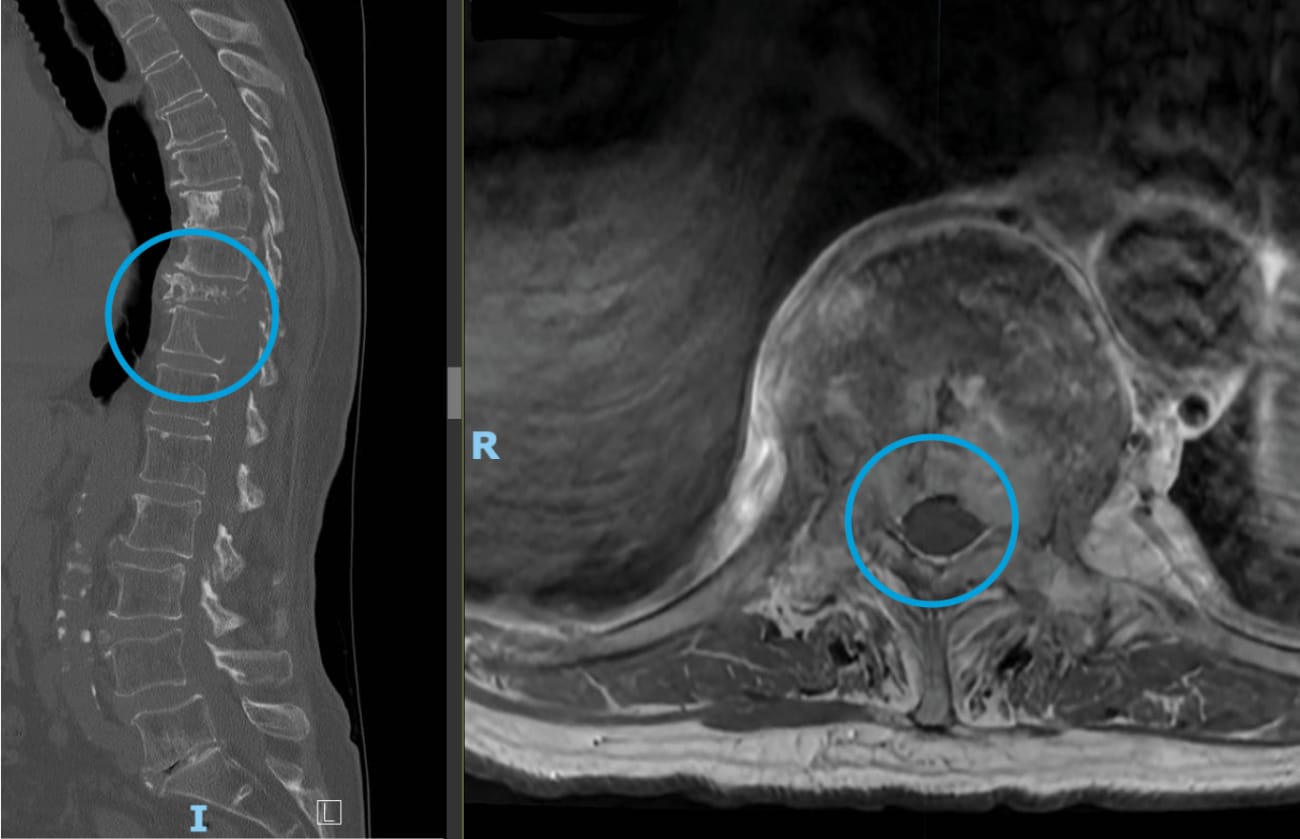

The patient, an active 80-year-old, had felt healthy for a dozen years after she had declined further treatment for breast cancer. But in late 2022, after undergoing hip replacement surgery, she developed back pain that became progressively worse. Initially suspecting complications from her recent operation, she tried to relieve the pain with exercise and stretching. But imaging showed something far more sinister: The breast cancer had metastasized to her thoracic spine, fracturing her T10 and T11 vertebrae, and invading her spinal canal.

In May 2023, Lubelski and his colleagues performed the surgery, assisted by a robotic navigation system. Utilizing the intraoperative navigation system, the surgeons placed the robot-guided screws to stabilize the patient’s spine, using carbon fiber screws instead of the usual titanium to minimize scatter and artifact on follow-up imaging studies. Then, Lubelski inserted a tubular dilator to carefully push muscle away from the affected area of the spinal column. To minimize damage to surrounding structures, he used an ultrasonic drill to cut away the tumor and decompress the spinal cord, rather than a traditional drill.